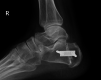

Introduction: Haglund's deformity (a prominence in the posterosuperior aspect of the calcaneum) is a known cause of posterior heel pain. Surgery is reserved for patients after failed conservative treatment. Zadek osteotomy is a dorsal-closing wedge osteotomy that reduces the posterior heel prominence. Zadek osteotomy is becoming a favored procedure, however, there are still relatively few studies focusing on patient-reported outcomes. Our main aim was to assess patient-reported outcomes following the Zadek osteotomy in refractory Haglund's deformity. Our secondary aim was to evaluate the correlation between patient outcomes and changes in their pre and postoperative Fowler-Philip and calcaneal pitch angles.

Methods: We conducted a retrospective review of 19 patients (20 heels) who underwent Zadek osteotomy by a single surgeon at a tertiary hospital over six years. Patient-reported outcomes were collected preoperatively and at 12 months postoperatively using the validated Manchester-Oxford foot questionnaire (MOXFQ) scoring system. We also calculated the difference in their pre and postoperative Fowler-Philip angles and calcaneal pitch using the picture archiving communication system.

Results: There was an average improvement of 108 points in the MOXFQ score at 12 months (P<0.05). There was no statistically significant change in calcaneal pitch. However, the Fowler-Phillip angle dropped with an average of 11.4 º (P<0.05). A decrease in the Fowler-Philip angle does improve patient-related outcome measurement scores, however, the relationship is not directly proportional with "r" measured at 0.23.